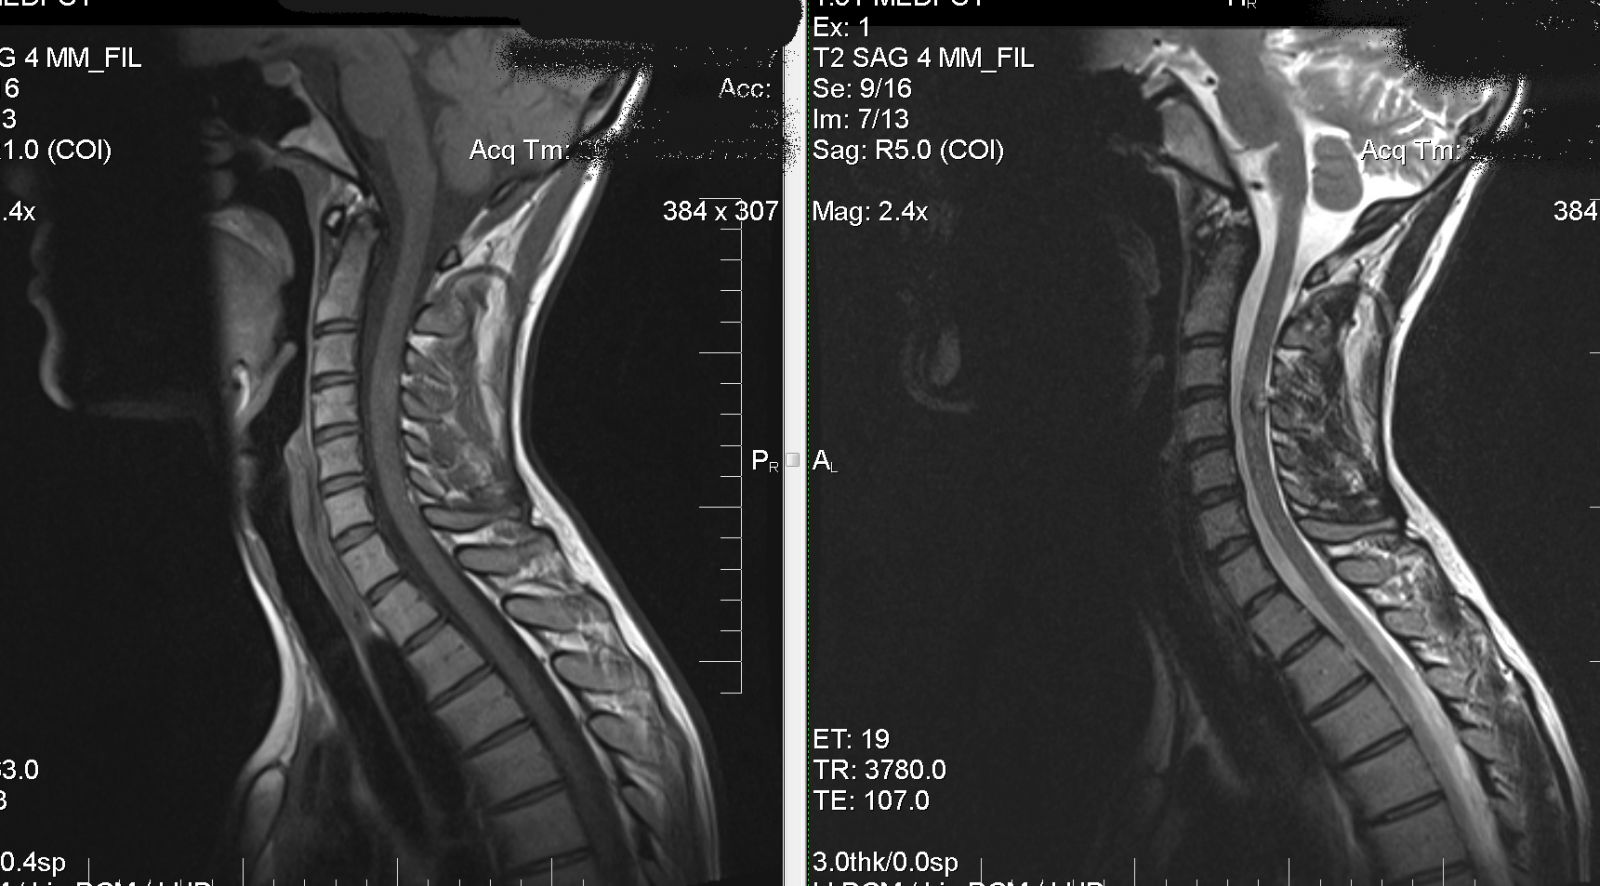

Магнитно-резонансная томография (говоря другими словами - МРТ) – это метод, который стремительно развивается и позволяет диагностировать множество заболеваний. Благодаря данному методу, вся современная медицина уже может с большой точностью определять диагноз на более ранней стадии любой болезни, или же, при таком условии, что какое либо другое заболевание никак не проявляется. МРТ непосредственно шейного отдела позвоночника разрешает выявить даже самые малые дегенеративно-дистрофические разрушение в позвоночнике.

Какой либо другой метод в исследовании не сможет дать столько информации именно о тканях уже известного позвоночного столба так, как МРТ.

Такое исследование позволяет хорошо увидеть, непосредственно в каком состоянии находится спинной мозг у пациента, а также обнаружить воспаление или же сдавливание нервов и, конечно же, диагностировать в начале, когда только развиваются опухоли, или же хронические, острые и инфекционные заболевания непосредственно спинного мозга. А также дать оценку именно состоянию всех межпозвоночных дисков. Также МРТ помогает обнаружить все сосудистые изменения, грыжу,  дистрофию и другие различные заболевания в шейном отделе позвоночника.

Магнитно-резонансная томография шейного отдела позволяет исследовать весь позвоночник, а также мягкие ткани. Кроме этого, магнитно-резонансная томография  есть совершенно безопасной.